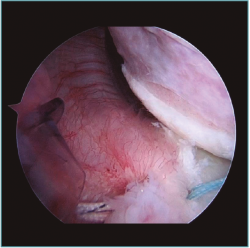

Creemos que el tratamiento quirúrgico de este grupo de jóvenes deportistas de contacto debe focalizarse en corregir la principal causa de su inestabilidad, que desde nuestro punto de vista es la laxitud articular del hombro(15,16)(Figura 1).

Figura 1. Visión desde portal lateral del hombro derecho. Paciente de 18 años con cuadro de inestabilidad de hombro recidivante. Se visualiza una gran laxitud articular con una lesión labral mínima.